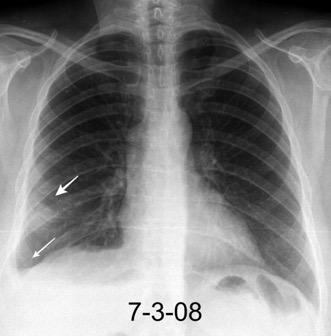

Nefrectomia derecha en 1996 por adenocarcinoma renal. Reseccion de metastasis pulmonar en LSI de carcinoma renal. Sospecha de nueva metástasis.

Granuloma de cuerpo extrano por hilo de sutura en situación cisural